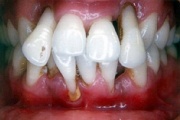

GAgP 25 aastasel suitsetaval puuduliku suuhügieeniga patsiendil